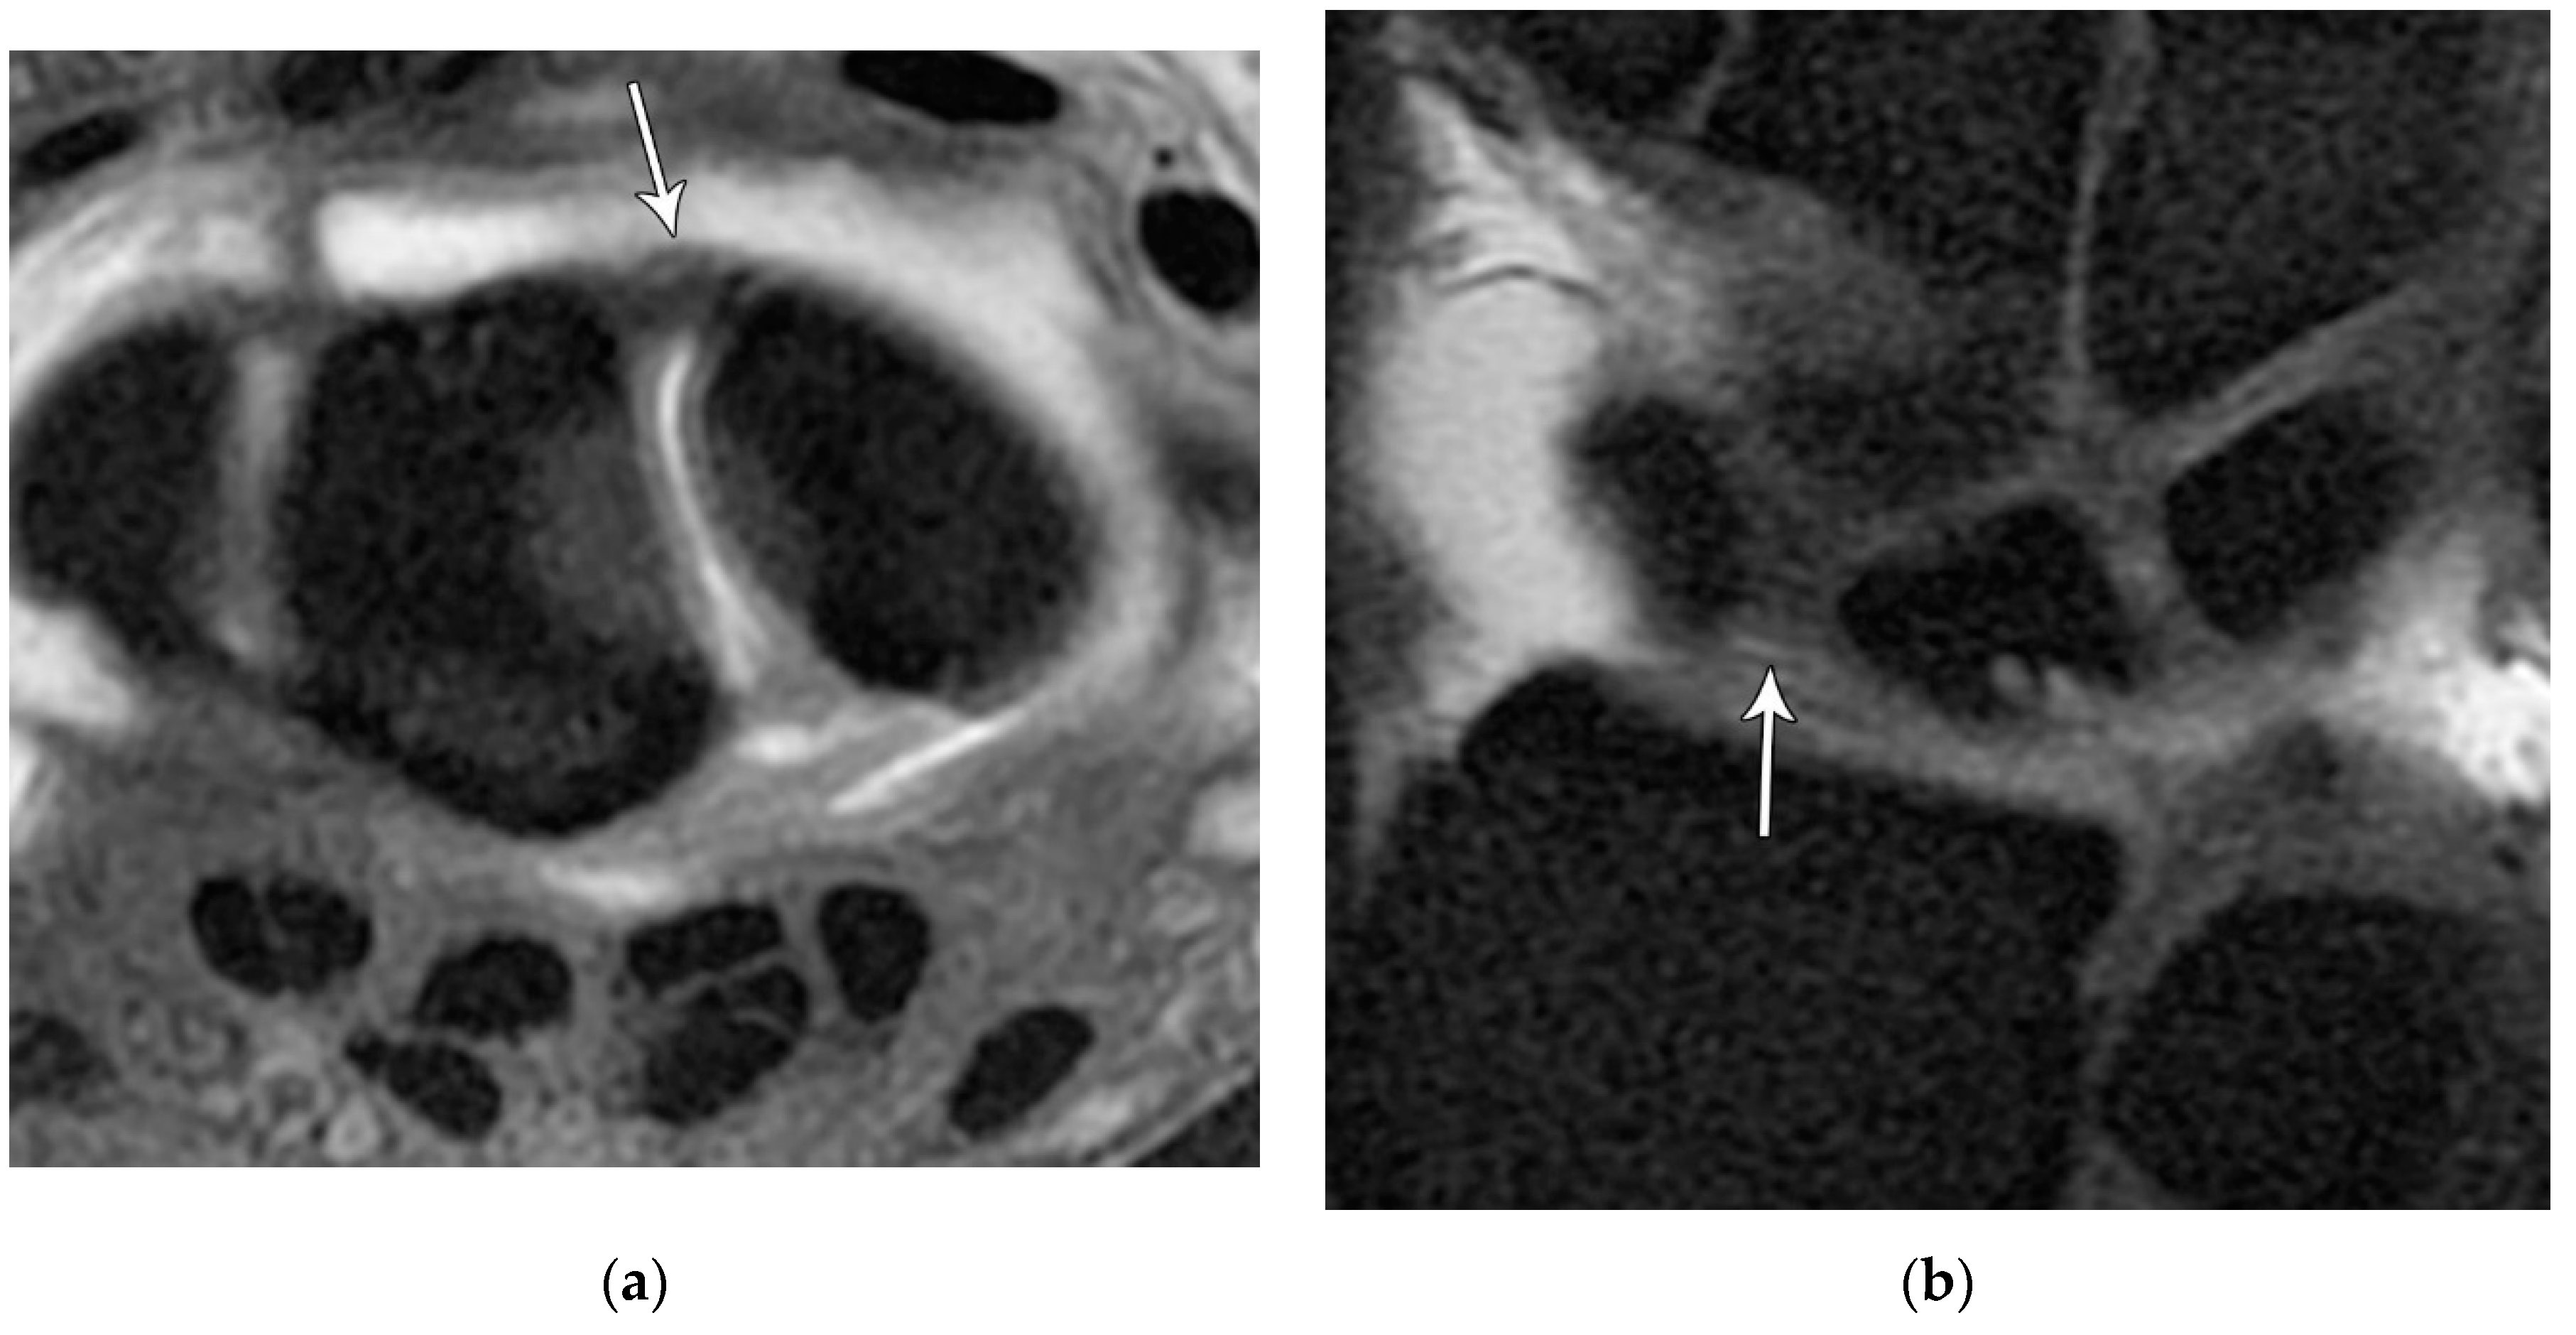

Figure 22. (a) Axial T1 FS MR arthrogram images showing a normal thick dorsal scapholunate ligament (arrow). (b) In a different patient, coronal T1 FS MR arthrogram images showing a normal thick dorsal scapholunate ligament (arrow).